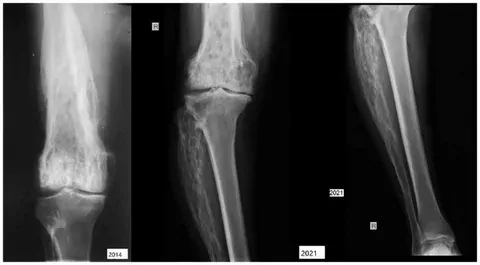

An X-ray showing bone changes from Paget's disease